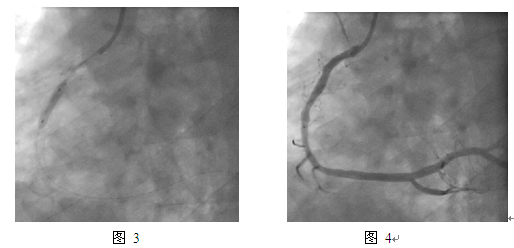

JR4.0指引导管,BMW导丝,预扩张球囊Fire Star 2.5mm x 15mm,最大20atm扩张;双导丝球囊Score Flex 3.5mm x 15mm,最大16atm扩张(图2);后扩张球囊Sapphire NC 3.75mm x 15mm,最大10atm;紫杉醇药物洗脱球囊(PEB)Sequent please 3.5mm x 20mm,最大18atm扩张,持续60s(图 3)。最终效果满意(图 4)。